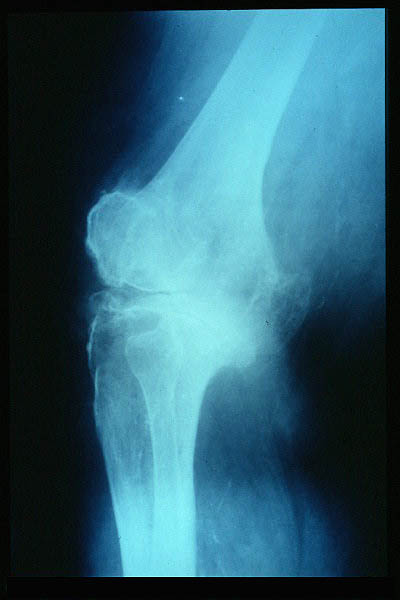

Carpo normal

ACT Alteraciones degenerativas en muñeca.